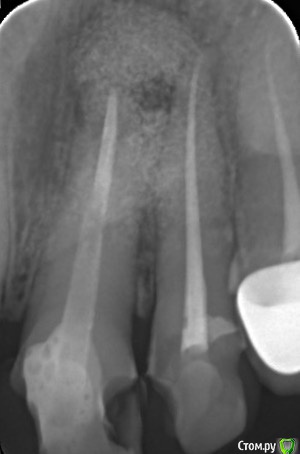

Добрый день, уважаемые специалисты. Прошу Вашего совета. 4 года назад на десне образовалась шишечка, рентген показал наличие кисты в области 21 (между 21 и 22) депульпированного зуба, киста была пролечена терапевтическим методом, позже была произведена реставрация зуба и установлен свш. Недавно на небе и десне опять образовались уплотнения. Уплотнение на небе очень болезненное, начались небольшие боли. Рентген опять показал наличие кисты, сделано кт - дыра в челюсти. Депульпировали 22й зуб и пропила антибиотики 5 дней, чтобы снять воспаление и сделать резекцию. Уплотнения после антибиотиков сдулись. Провели резекцию 8 дней назад, по словам доктора небной стенки в области больного зуба не осталось, заложили в дыру костный материал биос 0,5 гр., подпилили корень, убрали обнаруженный пломбировочный материал, пломбирование канала по обоюдному согласию с врачами не проводили. 22й зуб не трогали. Меня беспокоят несколько моментов:

Есть снимок и кт (как его прикладывать правда не знаю). Заранее всем спасибо, может я зря паникую.post-31623-0-45950300-1444599333_thumb.jpeg

Прикладываю снимок после резекции, сегодня была на консультации у другого специалиста, сказал, что мало прошло времени для беспокойства. Но он не работал с биос материалом и опыта по проведению резекций у него мало.

post-31623-0-71940100-1445705182_thumb.jpeg

Уважаемый Гарриевич :-) (извините, не знаю как к Вам обратиться), не могли бы вы посмотреть снимок? В ближайшее время я буду встречаться с доктором, проводившим резекцию, хотелось бы до встречи понять как обстоит дело (все плохо или жить буду :-)) и какой тактики, по вашему мнению, дальше придерживаться. Заранее спасибо и если, что извините за назойливость. Изменено пользователем Vilka

Тактику стоило выбрать изначально другую, но даже в вашем случае не смертельно. Время прошло действительно мало, возможно правильным решением будут регулярные осмотры у доктора, в динамике будет видно. На счёт ощущения крошек и прочего подсказать сложно.